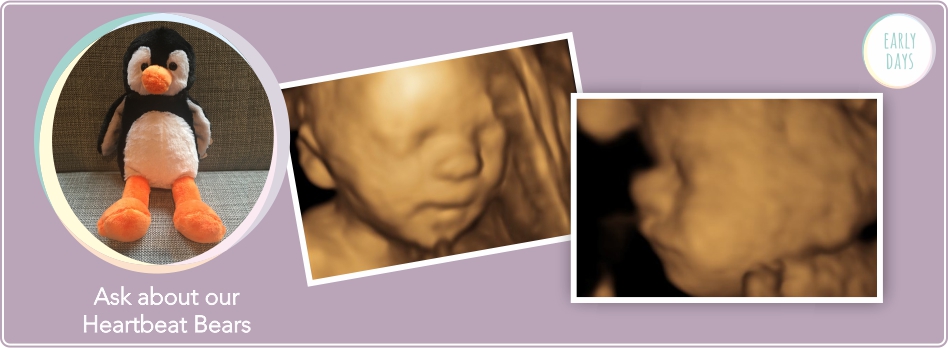

We can’t guarantee we will be able to obtain images of your baby in 3D/4D as there are factors which will limit our view of your baby in your womb – your baby’s position, number of babies, the amount of amniotic fluid surrounding your baby, position of the placenta and umbilical cord etc. We can perform 4D scans after 32 weeks, but this can reduce the possibility of seeing baby due to limited space within the womb.